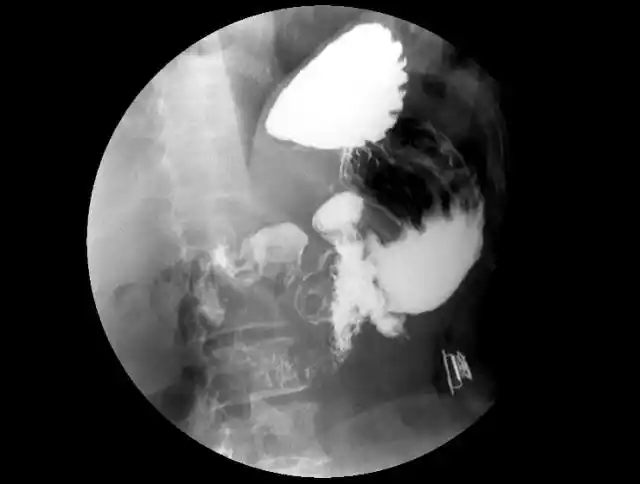

有没有小伙伴能帮忙看看片子,医生惜字如金,到现在我也不知道我的胃病

5 分钟读懂消化道造影片(胃篇)

吃煎馒头片,把胃划伤了,不知道是伤口还是溃疡,胸口就跟噎着东西一样

医院的x光片显示背痛,脊柱和臀部,创伤科扫描也显示胃和器官.